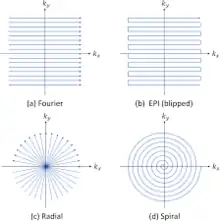

Efficient k-space sampling also decreases data collection time. Rectilinear scanning has become the standard k-space sampling method for MRI.[13] However, the process takes a relatively long time as it samples the entire k-space equally. Because of this delay, other sampling methods are used to capture real-time motion. Single shot echo planar imaging is one extremely fast sampling method in which all of the data for the MR image is collected from one RF pulse.[14] However, it is important to note that the EPI method is still a Cartesian sampling method, like the rectilinear scan, equally sampling the entire k-space. Spiral sampling, like EPI, only requires a single RF pulse to sample the entire k-space. Radial and spiral sampling are also used as methods to efficiently sample the k-space, with spiral also only requiring a single RF pulse to sample the k-space. Both radial and spiral sampling are more efficient than the Cartesian methods because they oversample low frequencies, which allows for general motion capture and better real-time image reconstruction.[10] Thus, radial or spiral sampling of the k-space are now the preferred methods for real-time MRI reconstruction.